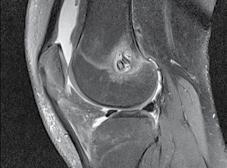

CT-ul cu reconstrucție tridimensională sau RMN genunchi relevă mult mai

bine complexitatea fracturii și dau posibilitatea unui planning preoperator superior estimării radiologice clasice(7). CT-ul este mai rapid și mai ușor de făcut, dar RMN decelează mai bine leziunile de menisc sau ligamentare.

Schatzker III, Osteosinteză cu șuruburi percutană

Schatzker VI, Reducere sângerândă și osteosinteză cu 2 plăci

fracturilor cu separare sau înfundare a platourilor tibiale, precum și a leziunilor de părți moi asociate ligamentare sau de menisc.

Se practică radiografii standard, examinare CT sau RMN.

Radiografiile se fac în cel puțin 3 incidențe: antero-posterioară, laterală și notch intercondilar.

Incidența antero-posterioară poate decela: o bandă osteoscerotică intensificată, specifică fracturii cu înfundare, separarea unui fragment osos, incongruență articulară femuro-tibială. O înfundare mai mare de 6 mm sau/și o incongruență articulară cu lărgirea acesteia mai mult de 5 mm sunt sugestive pentru leziuni de menisc lateral, ligament colateral lateral sau ligament încrucișat posterior(5). O înfundare sau lărgire articulară mai mare de 8 mm este deseori asociată cu o leziune de menisc medial(6).

Incidența laterală decelează traiecte de fractură postero-mediale.

În baza examenului radiologic au fost propuse mai multe clasificări, dar cea mai folosită este cea a lui Schatzker:

În fracturile Schatzker I, fără leziuni de menisc extern asociate este indicată reducerea și osteosinteza percutană cu șuruburi. Dacă leziunea de menisc este evidențiată pe RMN, se poate opta pentru reducere și osteosinteză percutană cu șuruburi asociată cu artroscopie(12), având rol de control al reducerii și curativ pentru leziunea de menisc, sau reducere deschisă și fixare internă cu placă și șuruburi.

La pacienții tineri cu fracturi Schatzker tip II și III se poate opta pentru reducere și osteosinteză percutană cu șuruburi asociată cu artroscopie. O altă variantă este cu grefă osoasă și reducere deschisă cu fixare internă cu placă și șuruburi. Controlul reducerii intraoperator se realizează artroscopic sau cu C arm.